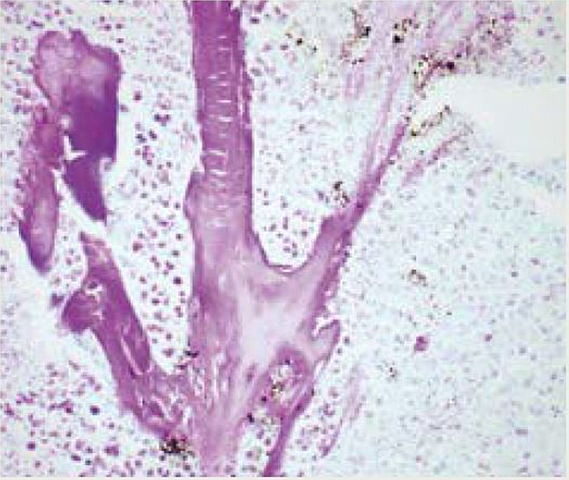

Robert Feulgen da a conocer al A.D.N como un componente importante de los cromosomas, lo hizo a través de la tinción(técnica para identificar material cromosómico).